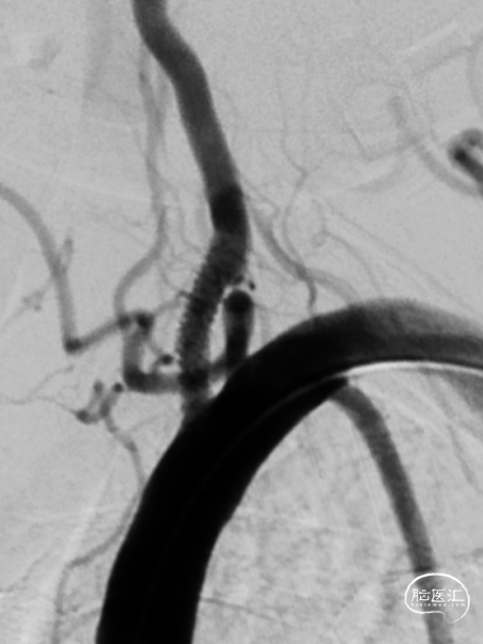

全脑血管造影DSA:双侧椎动脉起始段狭窄。远端供血不足。

患者双侧椎动脉均狭窄,左侧重度狭窄。左侧椎动脉充盈延迟、血流瘀滞,为闭塞前表现。所以权衡双侧椎动脉狭窄血管成型术的指征,优先处理左侧椎动脉起始段狭窄。为预防急性后循环缺血性卒中,在家属知情同意前提下行支架成形术。

8F导引导管到达锁骨下动脉。

微导丝通过椎动脉起始处狭窄段,到达椎动脉V3段。

沿微导丝送入2.5mm*15mm球囊预扩张狭窄处。

沿微导丝送入3.0mm*16mm Bridge椎动脉雷帕霉素靶向洗脱支架到达目标位置。经手推造影确认定位后,缓慢加压释放支架。